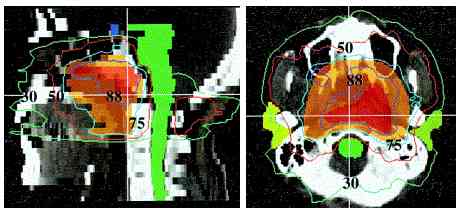

radiation isodose #1 , #2, #3, #4, #5 |